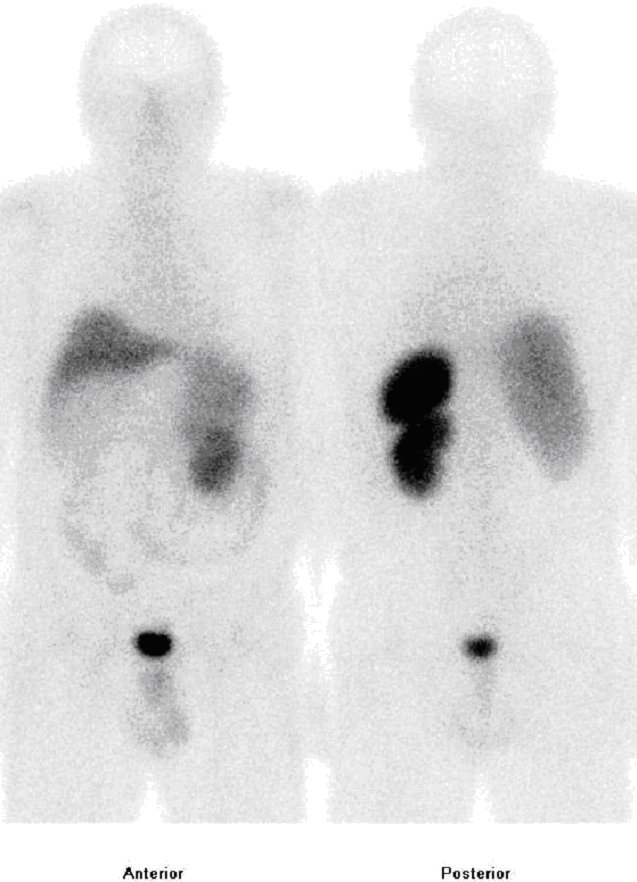

/ Obr.č.1: Celotělová scintigrafie v přední a zadní projekci 5 hod. po aplikaci radioindikátoru.

Scintigrafie Octreoscanem:

I.v. jsme aplikovali 220 MBq analogu somatostatinu značeného 111In

(přípravek OctreoScan firmy Mallinckrodt Medical) a provedli pomocí dvoudetektorové hybridní tomografické kamery Symbia T2 (SPECT/CT) firmy Siemens opatřené kolimátory pro střední energie planární celotělovou scintigrafii za 5 hod. a za 24 hod. a cílenou tomografickou scintigrafii (SPECT) břicha a pánve kombinovanou s CT za 5 a 24 hodiny

(obr. 1, 2, 3, 4).

Prokazujeme patologické ložisko zvýšené depozice radioaktivity v pravém

hypogastriu v oblasti céka..

Závěr: patologické ložisko se zvýšenou denzitou somatostatinových

receptorů v popsané lokalizaci odpovídající tumoroznímu postižení –

jedná se o neuroendokrinní nádor.